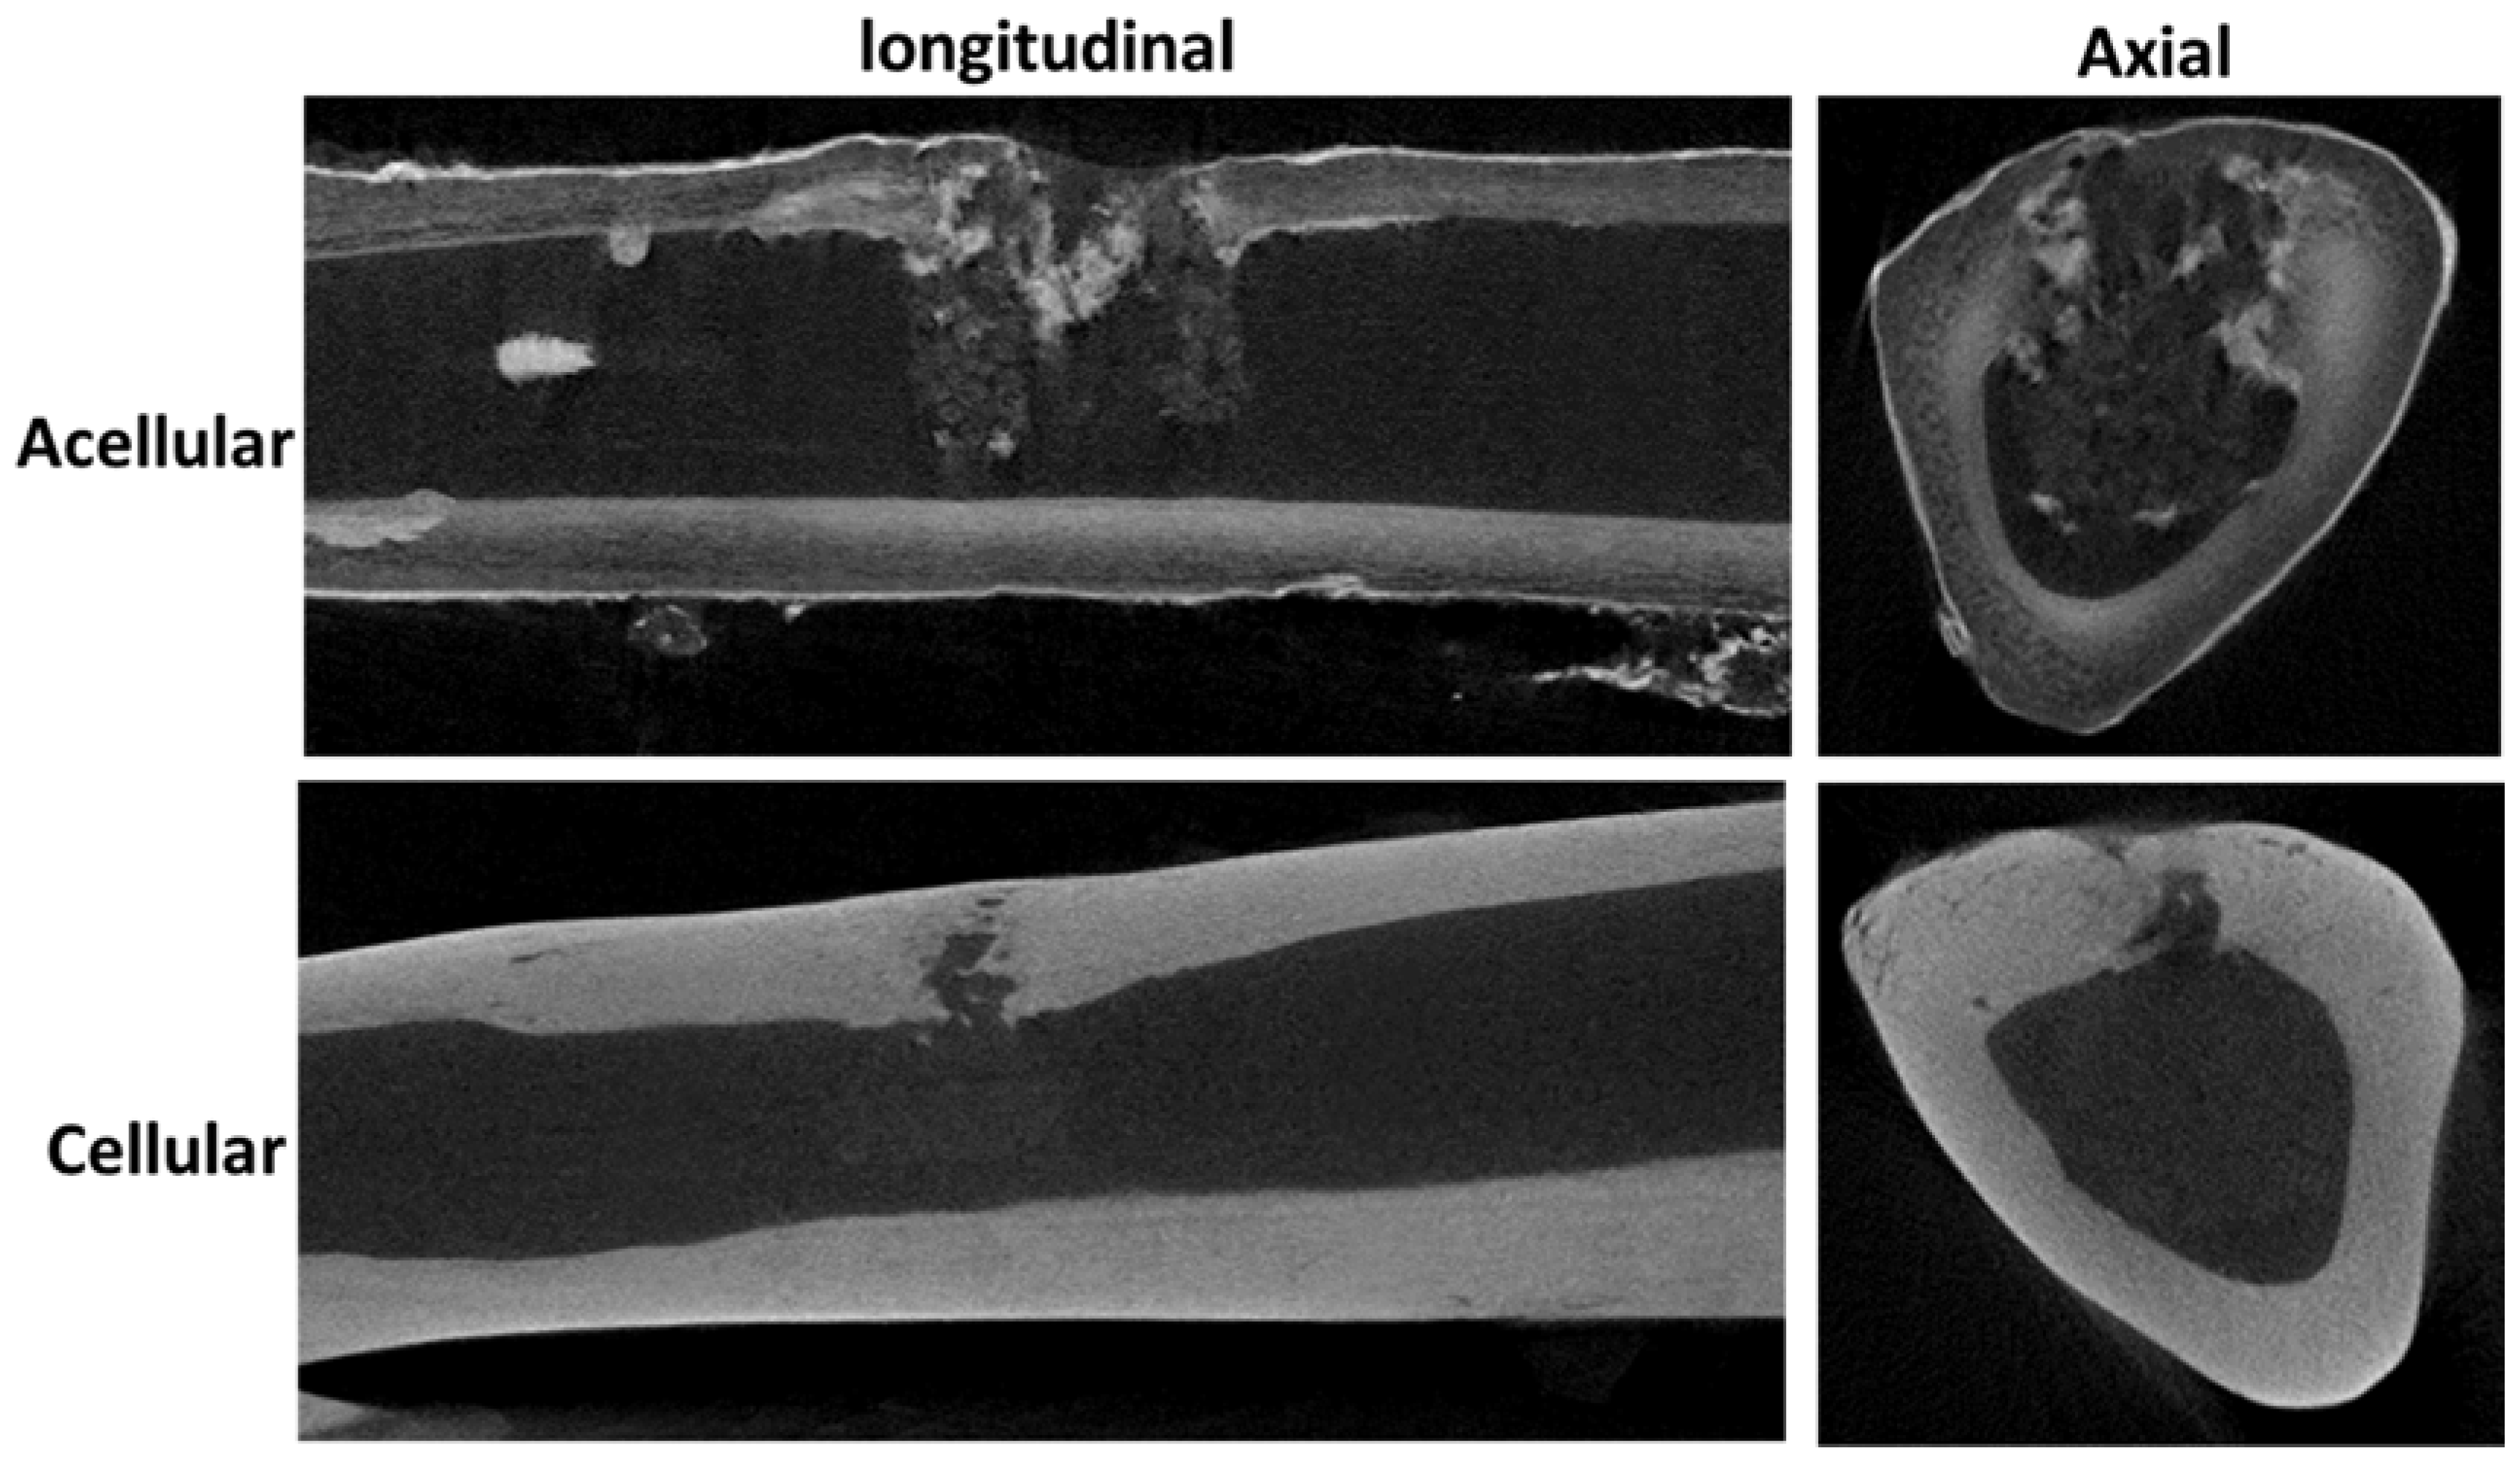

3.7. In Vivo Animal Studies